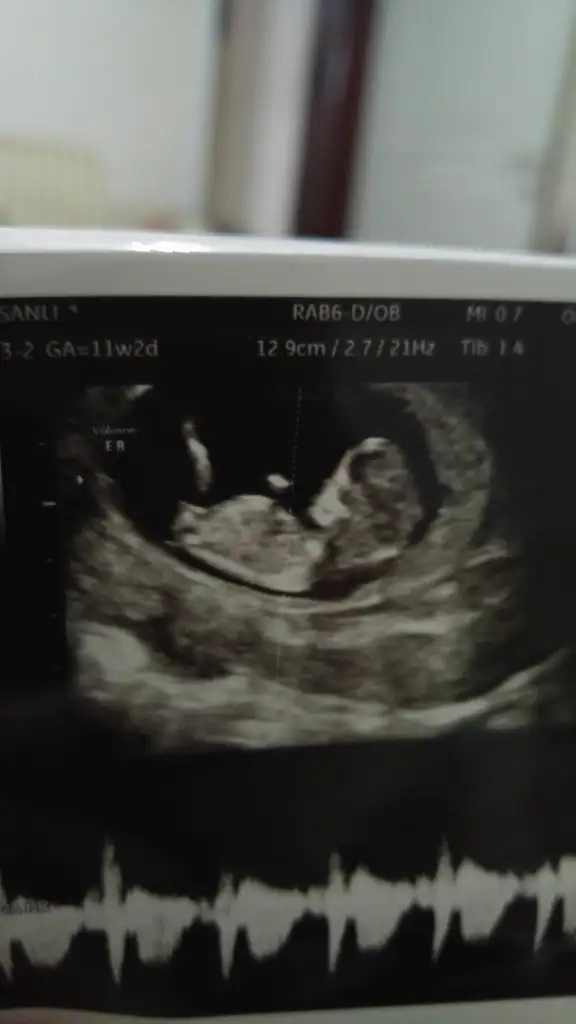

Teşekkürler uc tane usg var şuan elimde bgnun paylaşıyorum hemen, heyecanla yorumunuzu bekliyorum 😊😊😊💕

• 20200127_195653_HDR.webp

20200127_195653_HDR.webp

11,6 KB · Görüntüleme: 39

Evet ilk hayırlısıyla 12 de tekrar paylasicam bakalim degisiklik olucak mi 😊 hislerim erkek yonunde isteğimse kız kısmet artık